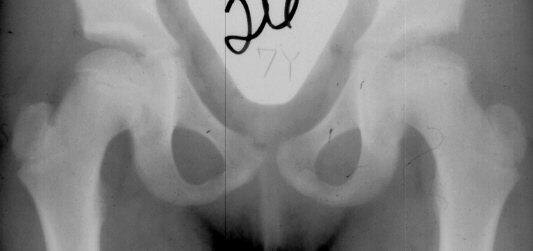

The progression of the hip is documented by x-rays taken at 1 year of age, 2 years of age, 3 years of

age, 5 years of age, 7 years of age, then at ten years of age, early closure of the lateral portion of proximal growth plate observed. Coxa valga was also observed.

The initial changes in the ossific center may follow exactly those seen in Group I, but in addition there is damage to the lateral part of the physis. The early roentgenographic signs indicating lateral physeal damage are: (1) lateral ossification, (2) lateral physeal irregularity and bridging, (3) lateral notching of the epiphysis, and (4) a lateral metaphyseal defect. The damage to the physis may remain dormant. By the age of ten years, however, valgus deformity of the head on the neck develops.( This type occurred in 35% of total AVN at AIDI.)